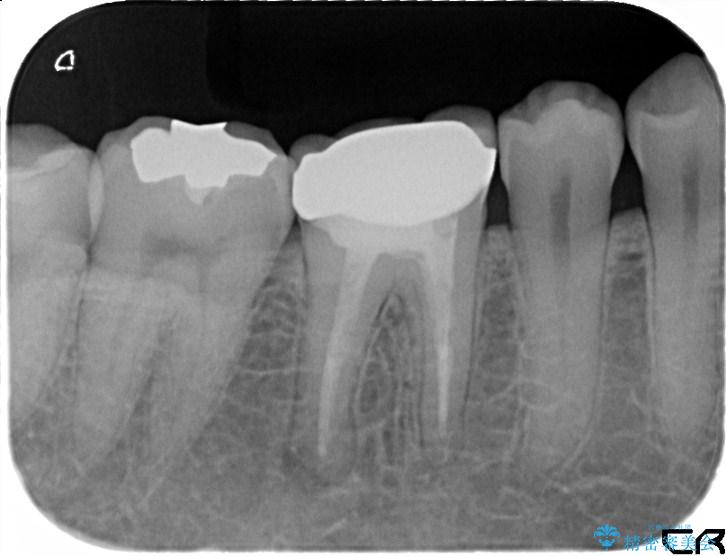

診査の結果、古い銀歯の隙間から新しい虫歯が広がっていました。ここは噛む力が強くかかる場所のため、このまま詰め物で治すと、部分的な詰め物では残存している自分の歯に負担が集中し、将来的に歯が割れてしまう「歯冠破折」のリスクが高い状態でした。

虫歯を丁寧に除去し、審美性・耐久性に優れたセラミッククラウンにやり替える治療計画を立案しました。

古い銀歯と中の虫歯をしっかりと取り除き、耐久性の高いセラミッククラウンで補強しました。

型取りには精密なシリコン材を使い、細菌の再侵入を防ぎます。